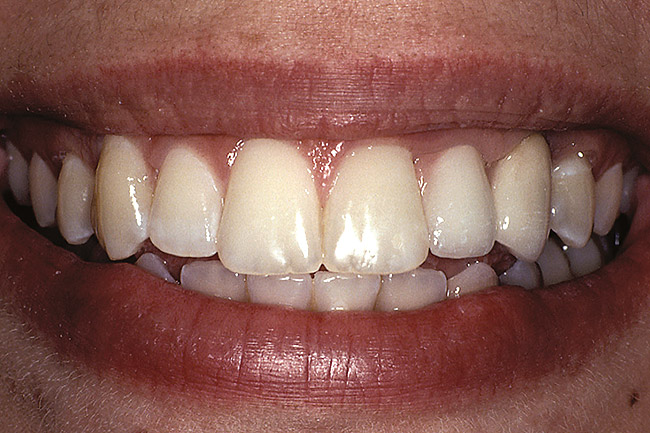

Figure 5  A patient presented needing both centrals extracted. Note the excellent papillary height and free gingival margin location.

Figure 5

Figure 9  The final restorations exhibit a minimal 1-mm to 1.5-mm change in papilla height when compared with the pre-extraction height.

Figure 9